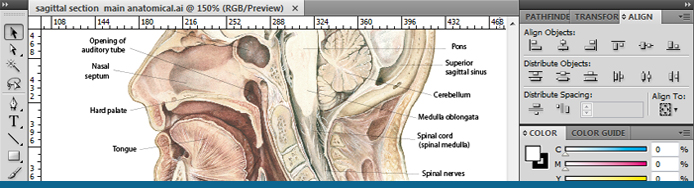

I then trained at Guy's and St. Bartholomew's Hospitals, London (Medical Artists Association course), specialising in the study of anatomy and physiology to produce surgical, anatomical, and editorial illustrations.

I produce artwork in a variety of styles and mediums, ranging from simple line drawings to full colour illustrations. Traditional techniques include pen and ink, pencil, coloured pencils, water colour and gouache. Digital techniques include artwork produced in Adobe Illustrator and Photoshop.